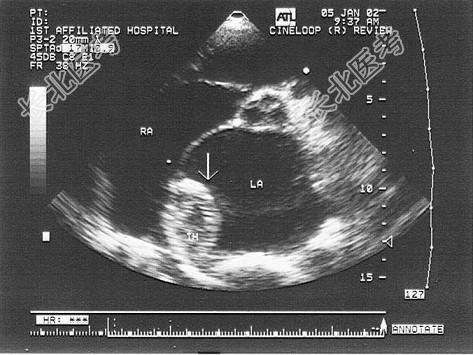

- 单项选择题患者有风心病史,该病可能诊断是 ( )

A、左房黏液瘤

B、左房良性肿瘤

C、左房赘生物

D、左房血栓

E、以上都不是